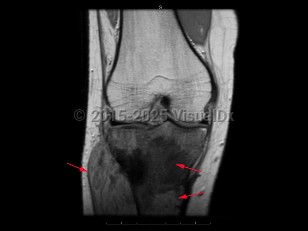

Osteosarcoma in Adult

The most common malignant tumor of bone. It arises from osteoblastic cells. Patients typically present with bone pain or a mass. The long bones are most commonly affected, and the tumor frequently metastasizes to other locations, especially the lung. Osteosarcoma is most common in males under 30 years of age. It can also occur secondary to medical conditions such as Paget disease and prior radiotherapy. Osteosarcoma is treated with chemotherapy and surgical excision of the primary tumor. With treatment, overall survival is approximately 60%-80%.